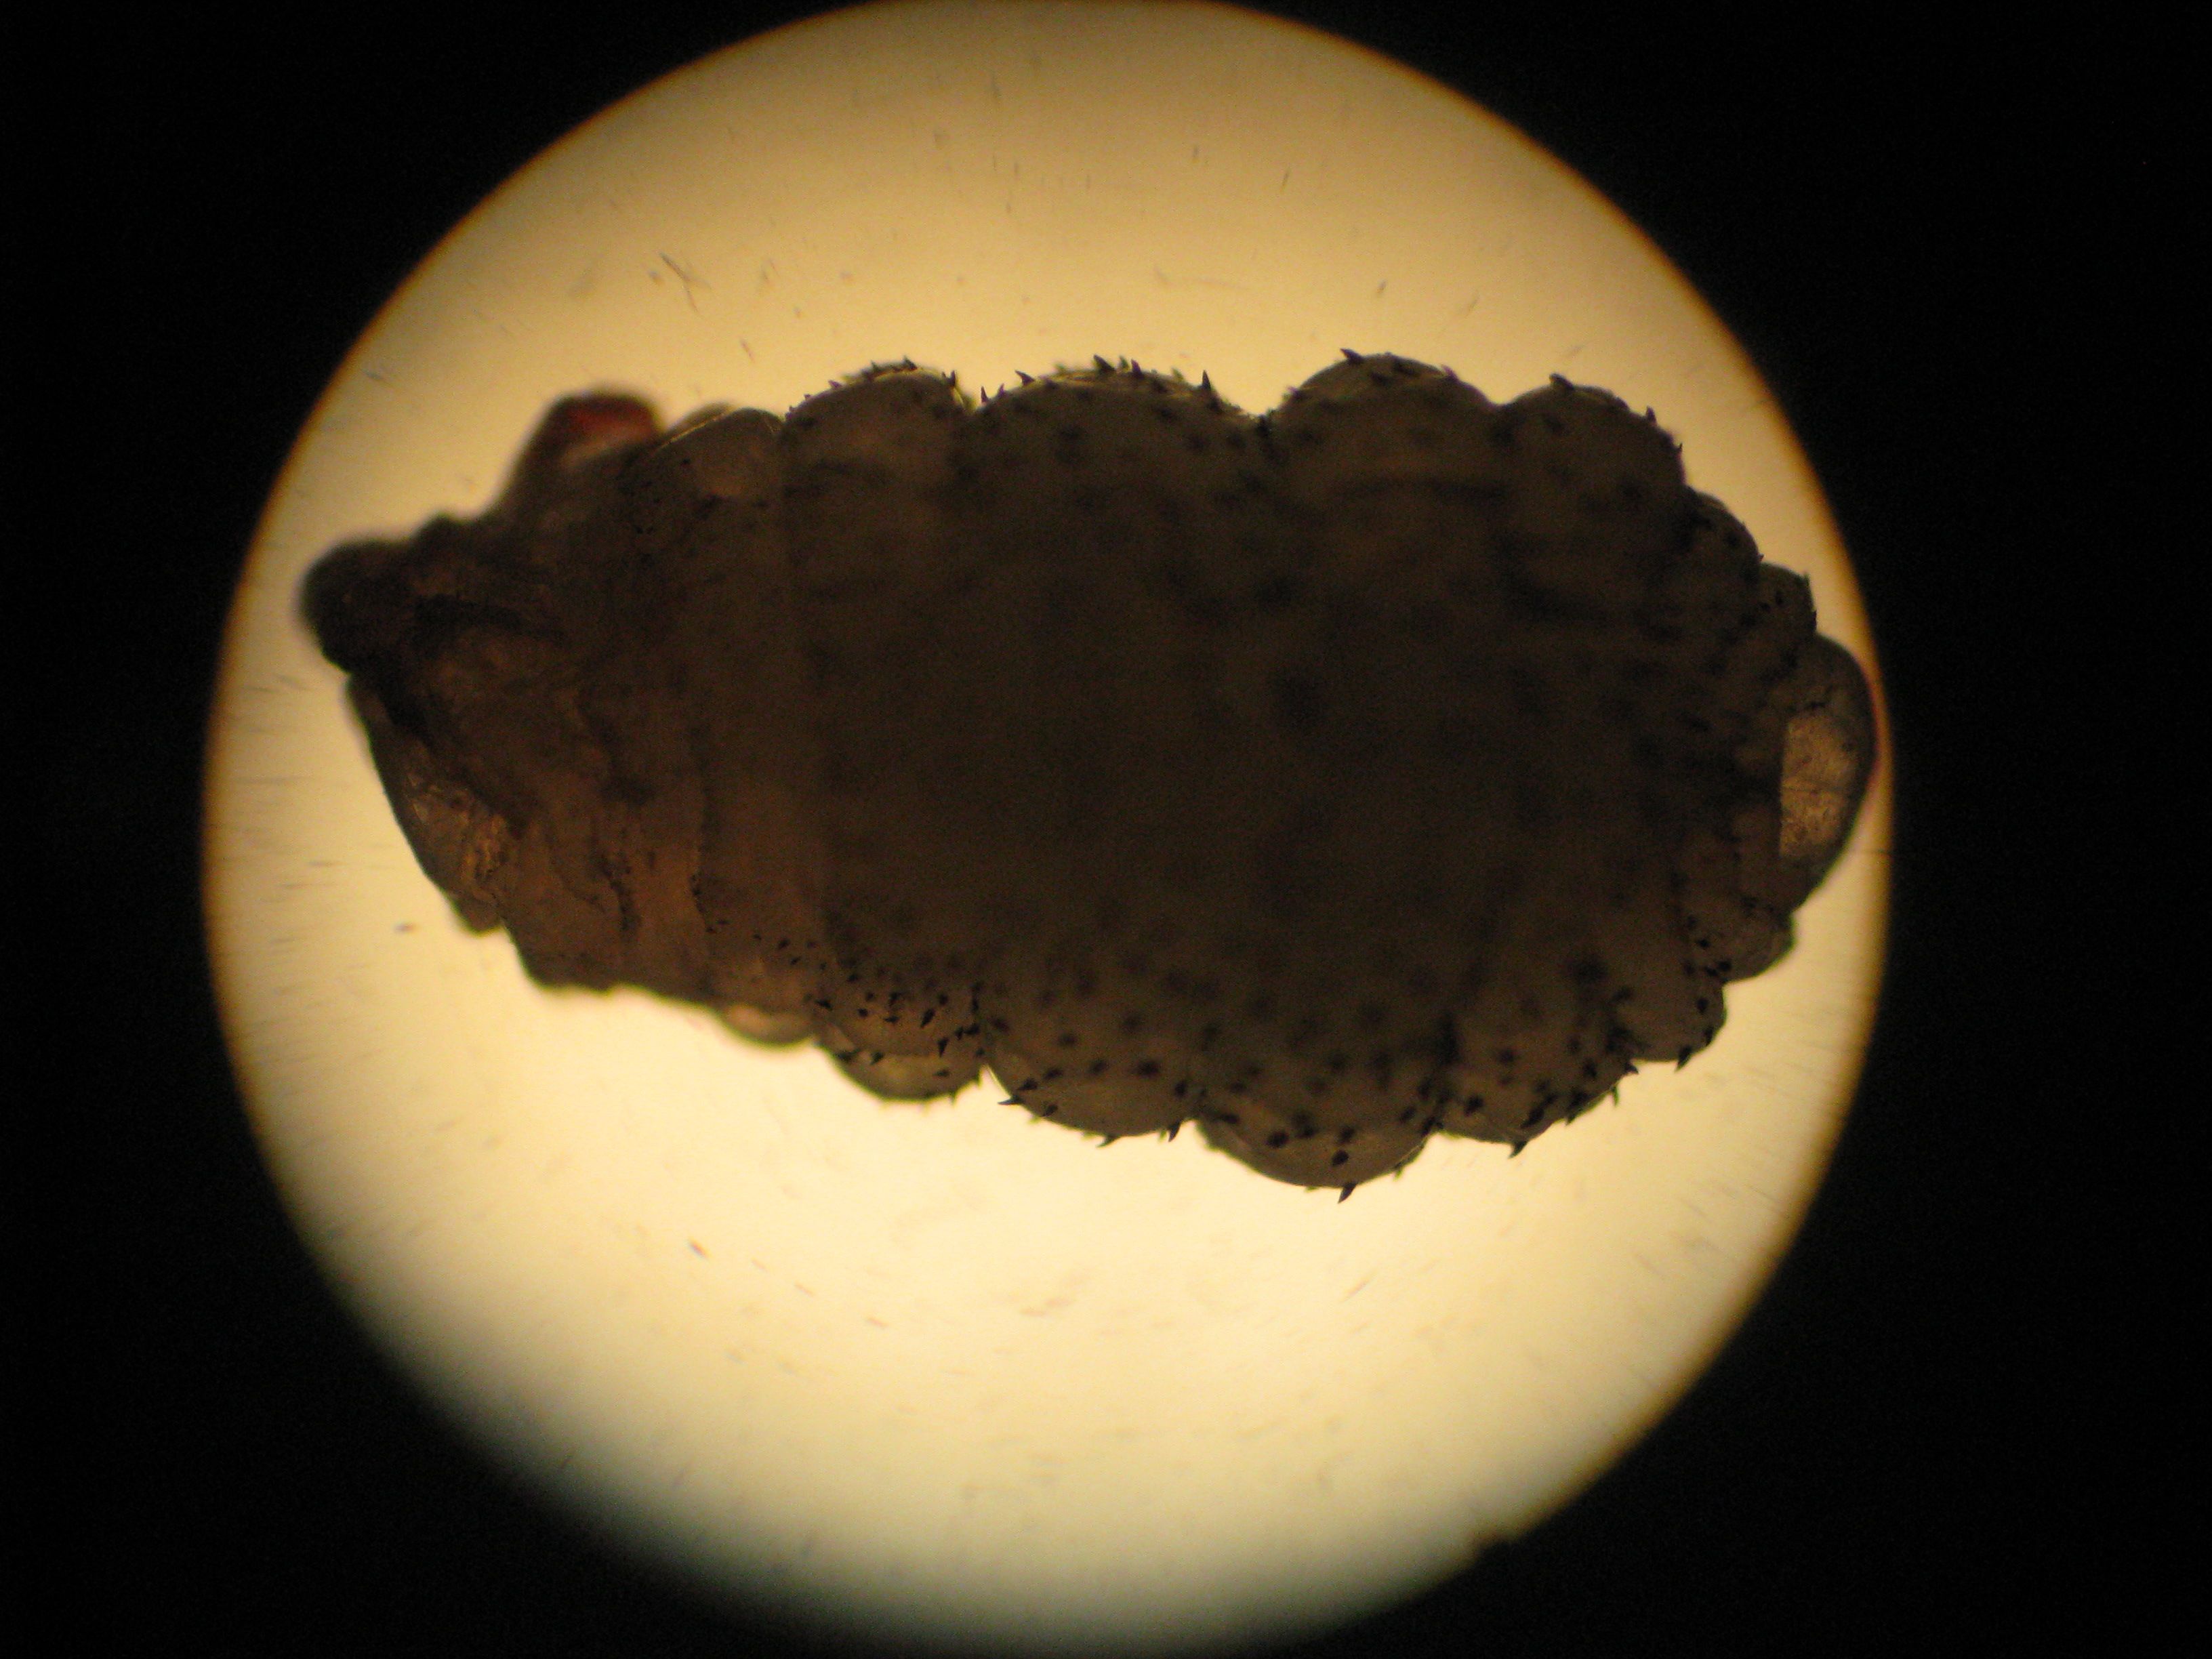

What is this 3 mm “lump” and what is the diagnosis?

This unfortunate traveler has myiasis, which is the medical term for parasitic infestation of a mammal by fly larva. In Tanzania (and most of East and Central Africa), the most common fly that causes this condition is Cordylobia anthropophaga, also known as the tumbu fly or putzi fly. The fly lays its eggs on soil or damp clothes (usually clothes hung out to dry), and the larva – which hatch out in 2-3 days – will penetrate the unbroken skin of mammals (or humans) that they come into contact with, creating a boil. In the South American variant, the botfly (most commonly Dermatobia hominis) lays its eggs on an intermediate vector such as a mosquito, which transmits the subsequently hatched larva to humans or other mammals.

Of course, that’s a case of myiasis, and that’s a fly larva. What would be really impressive is to be able to ID the species of the fly, but I can’t. I’m sure you’ll enlighten us soon enough. 😉

Actually, the geography helps in determining the species of fly, although to only a limited extent. It will probably take an entomologist to tell based on appearance alone.